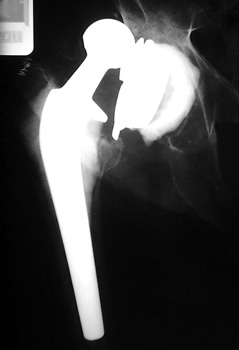

Dislocated total hip replacement